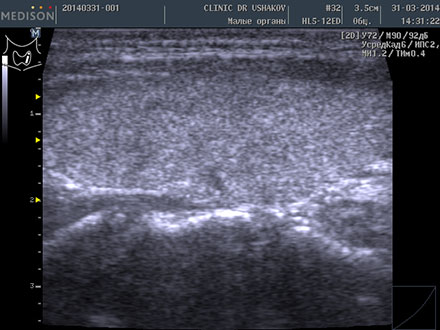

Пациентка К., 39 лет. При обследовании выявлены явления гипотиреоза и аутоиммунного тиреоидита. Через 1,5 года после лечебных мероприятий (в Клинике и соблюдение благоприятных условий) вместе с улучшением самочувствия произошло значительное восстановление щитовидной железы. В период лечения в связи с компенсированностью организма и гормонального обмена (Т4св. и Т3св.) и оздоровительным образом жизни медикаменты не применялись.

До лечения тиреоидита Анализ крови 9.06.2012 ТТГ 32 мЕд/л, Т4 св. 0,85 нг/дл АТ-ТПО 2113 ЕД/л | После лечения тиреоидита Анализ крови 15.01.2014 ТТГ 3,09 мЕд/л, Т4 св. 1,09 нг/дл АТ-ТПО 31,8 ЕД/л |

| В левой доле (в сосудистом режиме; ЦДК) заметно усиление кровотока ― свойственно избыточному напряжению железы | В левой доле (в сосудистом режиме; ЦДК) кровоток восстановился до оптимальной интенсивности ― нормальное состояние железы |